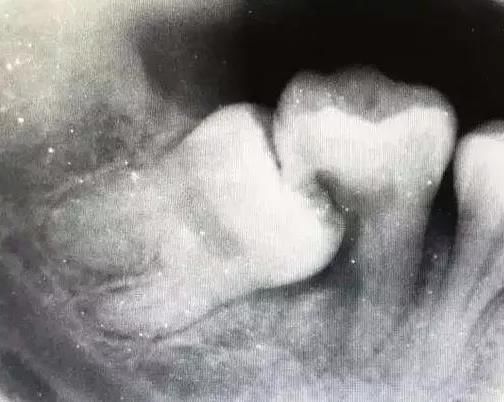

上图的智齿已经完全长出了,也已经蛀掉了,所以这种情况就要赶紧找牙医去拔掉,否则还会连累第二磨牙也一起蛀牙,那就更麻烦了。

以上是阻生智齿